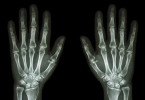

• 手指关节疼痛肿胀是类风湿吗

手指关节疼痛肿胀是类风湿吗

手指关节疼痛肿胀可能是类风湿关节炎,但也可能与其他疾病或损伤有关。类风湿关节炎是一种自身免疫性疾病,主要症状包括关节疼痛、肿胀和僵硬,尤其是早晨僵硬持续超过一小时。其他可能的原因包括骨关节炎、痛风或外 ...